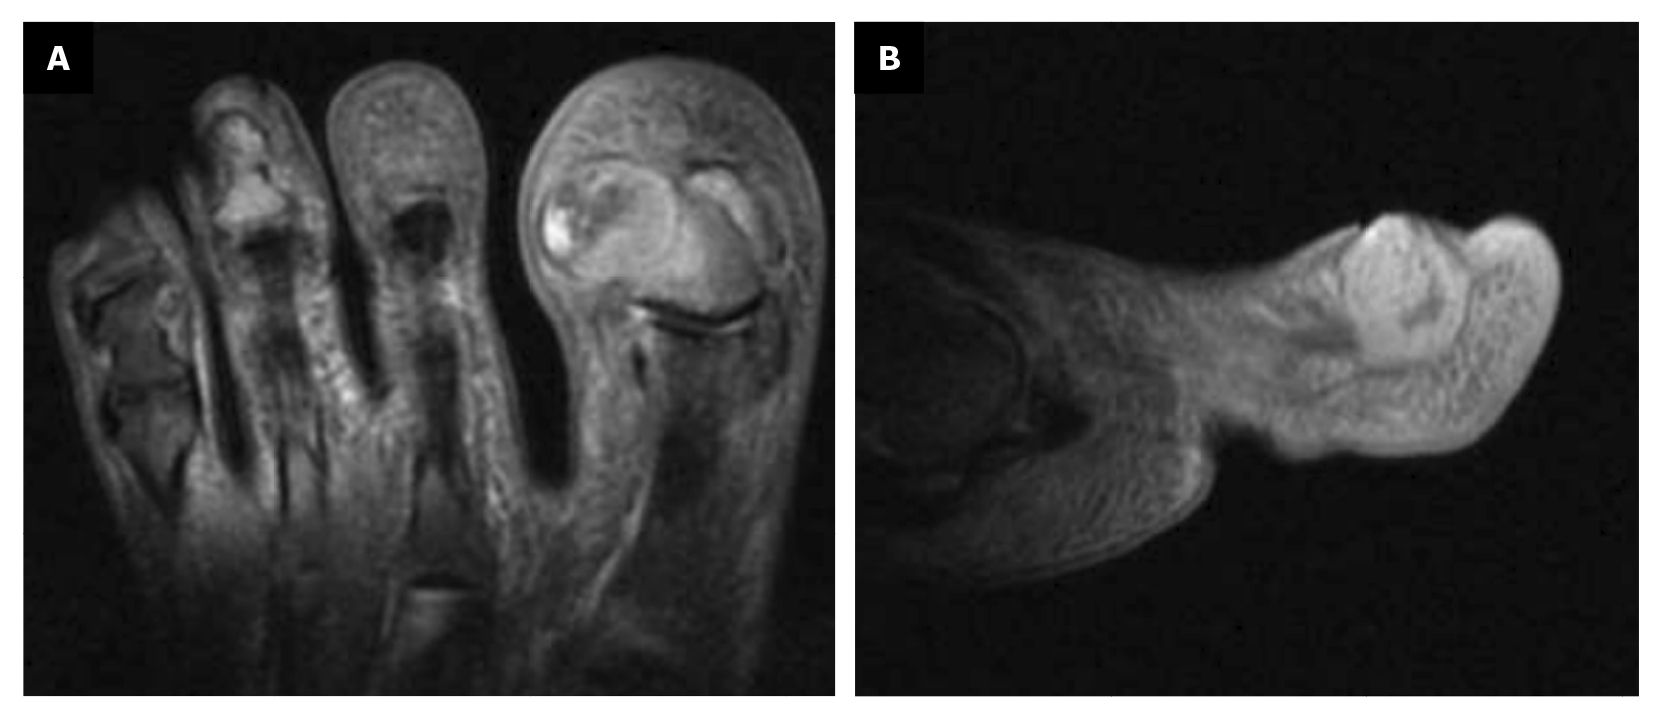

En el transcurso de 3 semanas después de la tercera intervención, la paciente refiere recidiva de la lesión y de la sintomatología dolorosa (Figura 7). La paciente decide acudir a servicio de traumatología (febrero de 2023) donde se solicita la realización de resonancia magnética nuclear (T2FS y DPFATSAT). En ella, se aprecia masa ocupante en el tercio lateral del primer dedo con bordes bien definidos y afectación ósea (Figura 8) con el siguiente informe: “A nivel de la falange distal del primer dedo en la región ungueal impresiona solución de continuidad cutánea con colección heterogénea, densa de 15 mm × 14 mm que se ubica en la región lateral de partes blandas parafalángicas, remodela el hueso y se pone en contacto con el tendón flexor, pudiera corresponderse con absceso/colección flemonosa postquirúrgica. Impresiona algo de edema óseo en falange distal sin descartar completamente incipiente osteomielitis. A confrontar con antecedentes y protocolo quirúrgico realizado”.

Figura 7. Semana 21. Recidiva de la lesión tras fenolización.

Figura 8. Masa ocupante con afectación ósea; A: plano transverso; B: plano sagital.